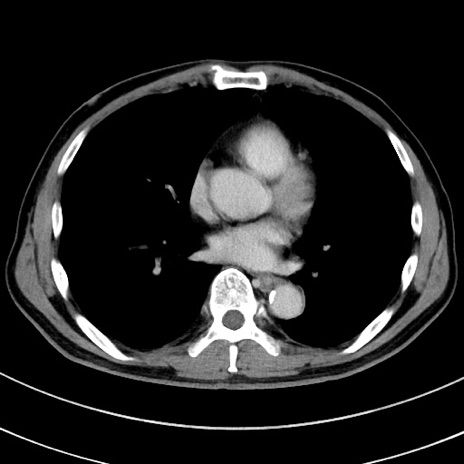

症例8(横断像)

【症例】 60歳代男性

【主訴】 黒色吐物

【現病歴】 4日前から嘔気自覚、2日前の朝食後にも嘔気あり、自分で手で嘔吐反射起こし嘔吐したところ血が混ざっていたため受診。

【既往歴】 5年前汎発性腹膜炎を伴う急性虫垂炎で手術、高血圧、前立腺肥大症、高脂血症

【身体所見】 腹部正中に手術癩痕あり 腹部平坦・軟圧痛なし膨満感あり

【データ】WBC 8400、CRP 4.54